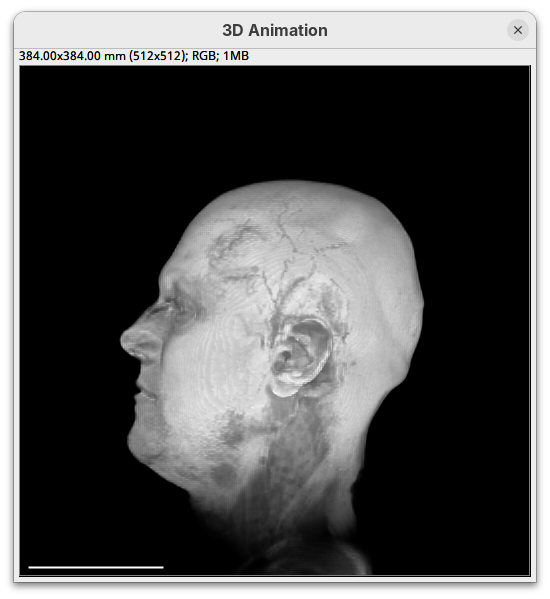

0.

By default 3Dscript sets the gamma value of alpha to 2.0. That’s a good default for fluorescence microscopy (see the next dataset below), but since this is MRI data, we need to tweak it a little differently.

- Set the alpha gamma value to

1.0.

Note that this improves the visualization as the head’s surface becomes better visible.

- Now set the alpha

maxto250.

The surface will become even more solid because we are defining that pixels that have a value above 250 will be fully opaque.

maxback to500.

Generally, setting the intensity and alpha to the same values is a good starting point for optimizing the rendering.